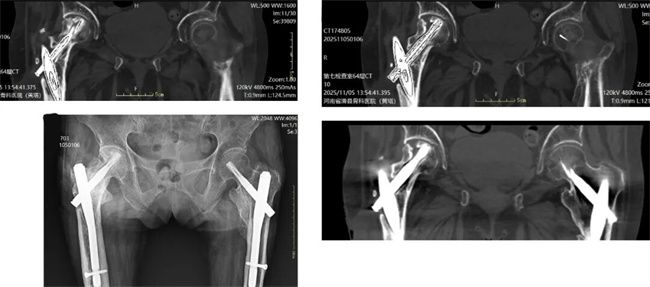

一、患者贾某某,女,77岁,患者双髋部术后,右侧窦道,少量黄稠液体流出,可见术后疤痕,活动受限。为求进一步治疗,来到我院请专家会诊,通过各位专家会诊查体、查看影像资料并细致认真的分析后,诊断为:右髋关节术后感染,窦道形成。建议:保守对症治疗。